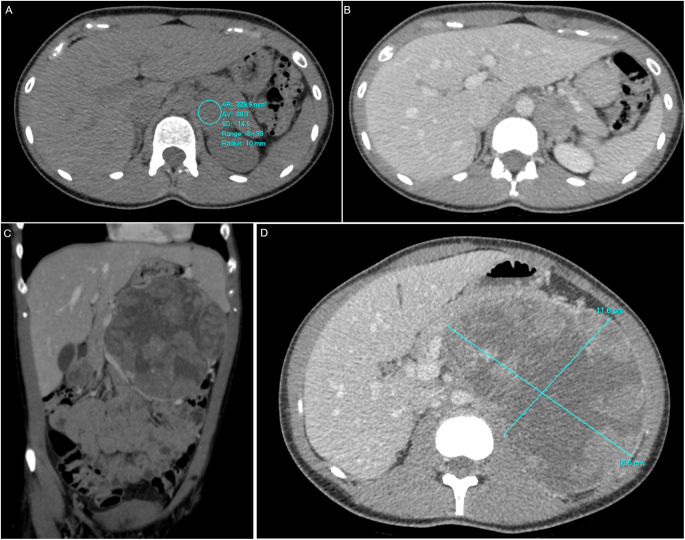

Summary: The new European Society of Endocrinology guidelines on the management of adrenal incidentalomas suggest discussion in a multidisciplinary meeting and consideration of additional imaging for homogenous lesions with a density >20 Hounsfield units (HU) and size <4 cm. We report a case of a 29-year-old woman who presented with benign-looking lesion on CT adrenals based on washout values, which was diagnosed as malignant on subsequent imaging. Initial hormonal work-up was normal. Two years later, the lesion had grown to 17 × 11 cm. Repeat hormonal work-up showed a raised urinary steroid profile and androstenedione along with an abnormal overnight dexamethasone suppression test. Our case report highlights a lesion being classified as benign based on washout recommendations subsequently diagnosed as adrenocortical carcinoma. We have reviewed our current clinical cohort and literature to assess the impact of the updated European guidelines on our practice, with particular reference to the use of HU.

Learning points: For the assessment of adrenal incidentalomas, CT washout values have limitations and should be interpreted with caution. Additional imaging may be required for lesions above 10 HU and this can vary according to centre expertise and availability. An adrenal lesion with a high HU value warrants follow-up imaging even if post-contrast washout values favour an adenoma. Adrenal incidentaloma are less common in younger patients, but are more likely to be clinically significant and/or malignant, so clinicians should have a lower threshold for surgery or interval imaging in indeterminate cases.